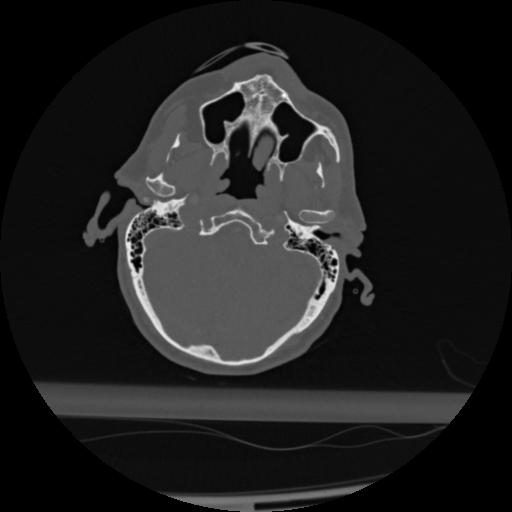

22 ANGIO,CE,Vol,0.5,ANGIO,,